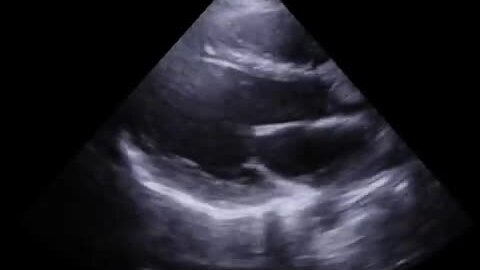

ЭХО-КГ сердца. Добавочные хорды левого желудочка (ДХЛЖ) подробности на канале ⤵️